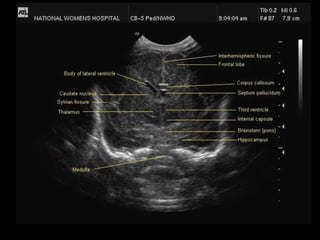

Angled Parasagittal View:

The shape of the lateral ventricle is the key landmark for this view.

The caudate nucleus lies below the floor of the frontal horn of the lateral ventricle; the

thalamus lies behind and below it.

The occipital horn of the lateral ventricle is filled with choroid plexus.

The choroid tucks up in the caudothalamic groove in the floor of the lateral ventricle and may be

echogenic.

Angled Parasagittal View: Theshape of the lateral ventricle is the key landmark for this view. The caudate nucleus lies below the floor of the frontal horn of the lateral ventricle; the thalamus lies behind and below it. The occipital horn of the lateral ventricle is filled with choroid plexus. The choroid tucks up in the caudothalamic groove in the floor of the lateral ventricle and may be echogenic.